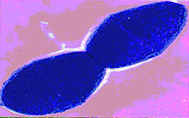

亞急性感染性心內膜炎疾病病因

亞急性感染性心內膜炎發病機理